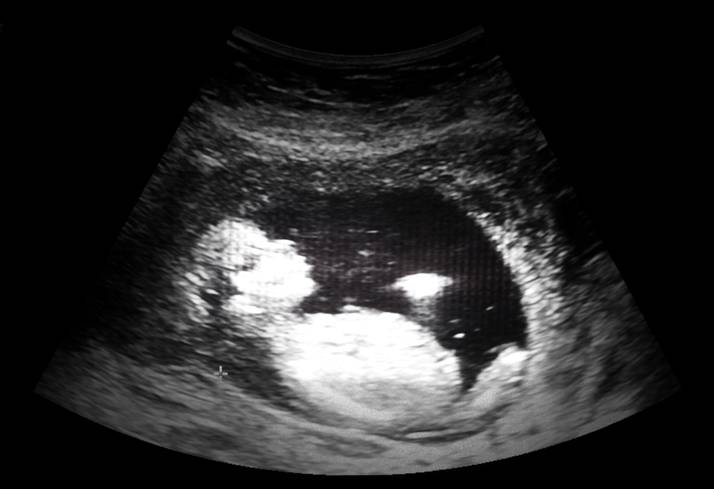

Mentre la chirurgia prenatale riesce a fare cose straordinarie, la comunità scientifica si interroga sulla necessità o meno dell’anestesia per i bambini che sono ancora nel grembo della mamma.

L’evoluzione delle tecniche chirurgiche che consentono, per esempio, di correggere la spina bifida in un bimbo ancora nell’utero materno, non prosegue parallelamente alla necessità di fornire un’anestesia al feto.

La maggior parte degli studi comportamentali e sulle reazioni endocrine si concentrano nel terzo trimestre. La seconda metà della gravidanza è il periodo in cui avvengono la maggior parte delle operazioni e i dati confermano che il feto può essere svegliato da stimoli esterni, ma le concentrazioni di ENIn non inducono un effetto anestetico.

Altri studi hanno dimostrato che uno stimolo doloroso sul feto aumenta lo stress, dopo le 20 settimane le vie del dolore sono già formate, quindi si caldeggia l’anestesia diretta del feto.